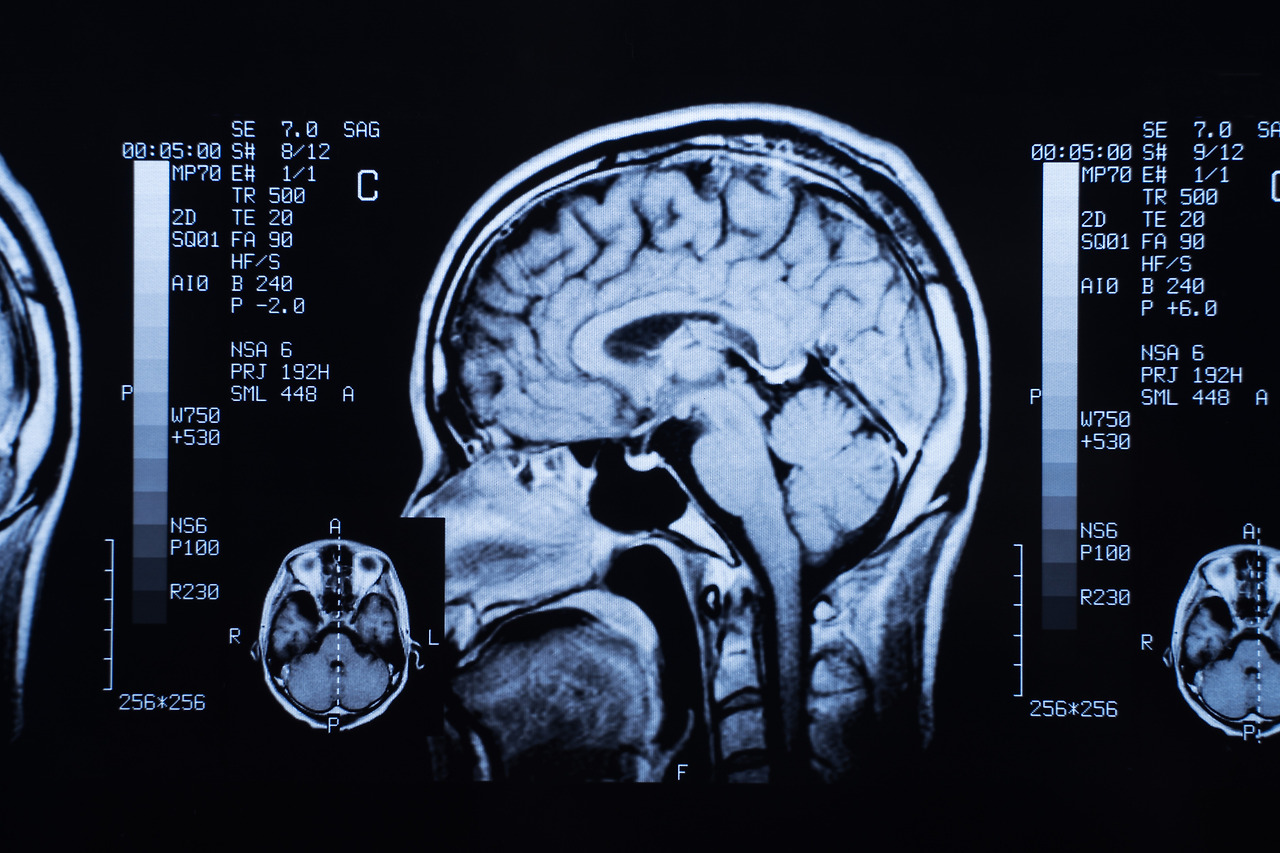

MRI는 CT와 달리 촬영 시간이 길고, 장비 구조상 소음이 발생하며 금속 제거가 필수적입니다. 검사 시간은 촬영 방식에 따라 달라지며 일반적으로 30~50분이 소요됩니다.

기본 촬영 시간

- 뇌 MRI 단독: 30~50분

- 장비 성능이 높을수록 촬영 시간 단축 가능